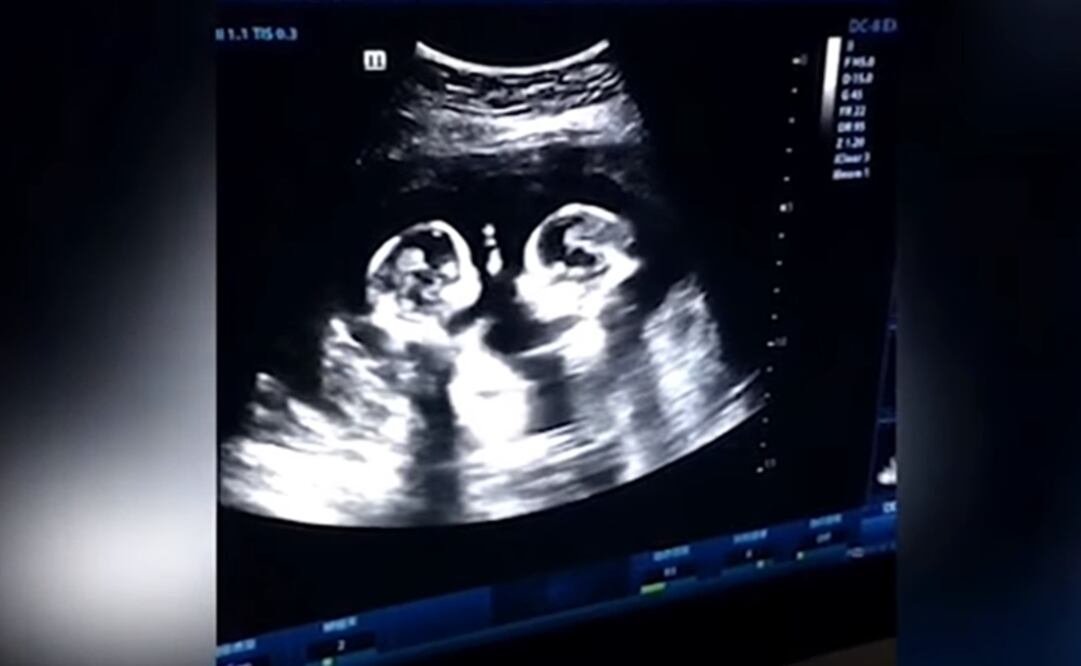

Este no fue el caso de unas gemelas de China , que terminaron convirtiéndose en las protagonistas de un clip que se viralizó en Youtube .

Se trata del video con la insólita "pelea" de unas gemelas en el vientre de su madre y que ha causando furor en redes sociales.

La escena fue registrada por Tao , padre de las niñas, quien dijo a la prensa local que grabó el hecho durante uno de los controles prenatales de su pareja a finales del año pasado.

Al joven, de 28 años de edad, le pareció gracioso ver que sus hijas no nacidas "boxeaban entre sí durante algunas rondas" , pero nunca pensó que iban a terminar convirtiéndose en "estrellas de Internet antes de nacer", señaló.

Desde que el video se compartió en Youtube, no ha hecho otra cosa que aumentar su popularidad; no obstante, no todo fue risas para las gemelas que fueron bautizadas como Cherry y Strawberry; se supo que ellas compartían el saco amniótico y la placenta, lo que es conocido como gemelos monoamnióticos monocoriales o gemelos Mo-Mo.

Este es uno de los embarazos múltiples más riesgosos, pues solo hay 50% de posibilidades de que los bebés sobrevivan después de las 26 semanas.

Afortunadamente, las niñas nacieron sin complicaciones el pasado 8 de abril gracias a una cesárea realizada a las 32 semanas de gestación, indicó el portal local Yangzhou Evening News.